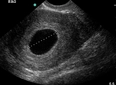

Sezaryen, doğum sırasında annenin karın bölgesine yapılan cerrahi bir müdahaledir. Bu yöntem, çeşitli tıbbi nedenlerle tercih edilebilir ve doğum sürecinde bazı riskleri beraberinde getirebilir. Sezaryen sonrasında karşılaşılabilecek en önemli komplikasyonlardan biri kanamadır. Bu makalede, sezaryen sonrası kanama belirtileri, nedenleri ve tedavi yöntemleri ele alınacaktır. Sezaryen Sonrası Kanama Nedir?Sezaryen sonrası kanama, doğumdan sonra kadının rahminden veya cerrahi kesiden kanama olması durumudur. Normal doğumda olduğu gibi, sezaryen sonrasında da kanama meydana gelebilir, ancak cerrahi müdahale nedeniyle riskler artar. Bu kanama, doğumdan sonraki ilk 24 saat içinde veya daha sonra ortaya çıkabilir. Sezaryen Sonrası Kanamanın BelirtileriSezaryen sonrası kanamanın belirtileri, şunları içerebilir:

SonuçSezaryen sonrası kanama, anne sağlığı açısından ciddi bir durumdur ve dikkatle izlenmesi gerekmektedir. Belirtilerin farkında olmak ve gerektiğinde tıbbi yardım almak, olası komplikasyonların önlenmesi açısından büyük önem taşır. Sezaryen sonrası bakım sürecinde, annelerin kendilerini ve bebeklerini korumak için sağlık uzmanları ile düzenli iletişimde olmaları önerilmektedir. Ekstra BilgilerSezaryen sonrası kanama ile ilgili risk faktörleri arasında, önceden geçirdiği sezaryen sayısı, obezite, anemi ve daha önce kanama öyküsü gibi durumlar yer alabilir. Bununla birlikte, sezaryen sonrası iyileşme sürecinin sağlıklı bir şekilde ilerlemesi için, annenin dinlenmesi, yeterli sıvı alımı ve dengeli beslenmesi de önemlidir. Sezaryen sonrası kanamanın önlenmesi için, hamilelik süresince düzenli doktor kontrolleri ve uygun prenatal bakım alınması önerilmektedir. |